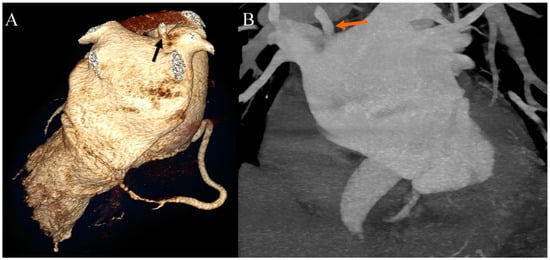

Ehlers–Danlos syndrome (EDS) encompasses a spectrum of heterogeneous, heritable disorders affecting connective tissue. According to the 2017 international classification of EDS, there are 13 subtypes. A rare 14th subtype was found in 2018. Each subtype has unique aspects, and a genetic cause has been identified in all subtypes except hypermobile EDS [1]. Clinical manifestations arise from the pervasive fragility and weakness of the soft connective tissue. Apart from manifestations in the skin, ligaments, joint and internal organs, there are subtypes of EDS which affect blood vessels and cardiac valves. These subtypes confer a higher risk of cardiac valve insufficiency, aneurysms, dissections, or ruptures of arteries, including coronary ruptures [2]. The estimated prevalence of EDS approximates 194.2 cases per 100,000 individuals [3]. Here, we present a case of a 34-year-old man with normal body weight, with hypermobile EDS, type 2 diabetes mellitus, chest deformity, aortic valve regurgitation, and aortic bulb aneurysm characterized by an axial diameter measuring approximately 5 cm (Figure 1). The patient had severe rotational scoliosis of the Th-L spine, with a significant deepening of the thoracic kyphosis and lumbar lordosis. There was a decrease in the AP dimension of the chest, a deformation of the ribs with a decrease in the width of some intercostal spaces, and a secondary widening of the width of other intercostal spaces. The patient underwent elective spine surgery to correct severe rotational scoliosis of the T-L spine. After postoperative rehabilitation, the patient underwent a thorough assessment of eligibility for aortic bulb aneurysm and aortic valve replacement surgeries. Consequently, a coronary computed tomography angiography (CCTA) was performed five months after the spinal surgical intervention. The CCTA revealed an absence of the left main (LM) and the right coronary artery (RCA) dominance. Significantly, the left circumflex artery (LCx) exhibited an ectopic origin from the right sinus of the valsalva, demonstrating a retroaortic course in the proximal segment and a typical course in the distal segments (Figure 2). Furthermore, the presence of a coronary–pulmonary arterial fistula (CPAF) in the CCTA was visualized. A vessel with an approximate diameter of 0.3 cm originated from the right sinus of the valsalva and progressed anteriorly and then towards the left, traversing anteriorly to the right ventricular outflow tract. Thereafter, this vessel was visible to the left of the main pulmonary artery, ultimately divided into multiple narrow segmentally aneurysmally dilated and tortuous fistula vessels. The fistula vessels showed communication with the proximal segment of the main pulmonary artery (Figure 3). Moreover, the imaging revealed the presence of an additional right pulmonary vein (Figure 4). The CCTA revealed calcifications within the aortic valve. The patient received a qualification card for surgical treatment, was informed about the high surgical risk, and is awaiting the operation.

Figure 3. Coronary artery computed tomography angiography. Coronary–pulmonary arterial fistula. (A) Volume-rendering technique reconstruction. Anterior-right view. The arrow indicates the proximal part of the fistula. (B) Volume-rendering technique reconstruction. Anterior-left view. The arrow indicates the distal part of the fistula. (C) Multiplanar reconstruction. Axial view. The arrow indicates the origin of the fistula from the right aortic bulb sinus. (D) Multiplanar reconstruction. Axial view. The arrow indicates the connection between the fistula and the main pulmonary artery.